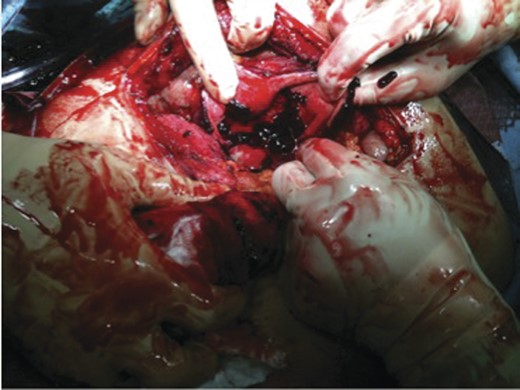

In the operating room a right Kocher incision was performed. Upon entering the peritoneal cavity a large haematoma was encountered with some old blood. Following the evacuation of the haematoma, the gallbladder was identified; it was massively distended with a haemorrhagic-appearing wall and had a tear in the fundus. Inside the gallbladder lumen clots and fresh blood was seen (Figs 3 and 4). It was clear that the bleeding cystic artery branch distended the gallbladder with blood leading to gallbladder rupture and free haemorrhage into the peritoneal cavity, with a total amount of evacuated haematoma of 2.5 L. A cholecystectomy was performed in a retrograde fashion, and a drain inserted before the closure of the abdomen. The patient was extubated and transferred to the recovery room in a stable condition. He did well post-operatively and was discharged home on the 6th post-operative day.